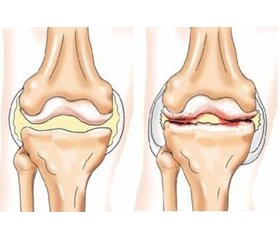

Остеоартроз (ОА) — найбільш поширене хронічне прогресуюче залежне від віку захворювання суглобів дегенеративно-дистрофічного та запального характеру, що є однією з основних причин втрати працездатності й інвалідності [1]. Йому притаманний високий рівень полі- та коморбідності, що характеризується віковою кількісною та якісною різноваріантністю. Це визначає клінічні, патофізіологічні, прогностичні та лікувально-профілактичні особливості ОА [2, 3]. За цих обставин як при ОА, так і при інших захворюваннях внутрішніх органів проблема дослідження коморбідності та поліморбідності визнана однією із ключових сучасної світової медицини [4, 5]. У низці досліджень показано, що при ОА найчастіше спостерігаються артеріальна гіпертензія (АГ), ішемічна хвороба серця (ІХС) та інші прояви атеросклерозу, ожиріння, жирова хвороба печінки, цукровий діабет (ЦД) 2-го типу, захворювання системи травлення [5, 7, 12]. Вплив ожиріння на прояви, патофізіологічні особливості, перебіг і результати лікувально-профілактичних заходів при ОА є загальновизнаним та широко висвітленим [2, 12–14]. Відомо також, що ожиріння є найбільш поширеною неінфекційною епідемією останніх десятиліть та водночас «колискою» десяти поширених і соціально значущих недуг: АГ, ІХС, інфаркту міокарда, інсульту, ЦД, ОА, подагри, жирової хвороби печінки, калькульозного холециститу і навіть, хоча рідко, онкологічних хвороб (у чоловіків — рак сигмоподібної кишки або простати, у жінок — гінекологічної сфери або молочних залоз). Такий ланцюг взаємопов’язаних уражень різних органів і систем має, імовірно, спільні неспецифічні патогенетичні ланки, ступінь та особливості яких залежатимуть від різних проявів будь-якого із зазначених захворювань та вікових особливостей метаболічних і регуляторних систем організму хворого.

Слід зазначити, що з віком у загальній сукупності вибірки зростали системність ОА (поліостеоартроз) та вираженість суглобового больового синдрому, ступінь рентгенологічних змін, а за наявності ЦД чи гіпотиреозу, як правило, виявляли торпідний характер перебігу та гірші результати лікування, третю їх ступінь за Келгреном — Лоуренсом.